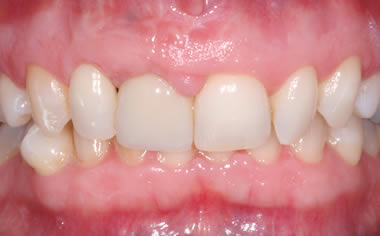

More front teeth replaced by dental implants

Case Three (4 images)